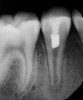

(5.) Radiograph of tooth No. 29 taken 1 year after regenerative endodontic treatment.

Figure 5

Following the induction of bleeding, a resorbable collagen matrix is placed over the blood clot. Next, a bioceramic material is placed directly over the collagen matrix, a glass ionomer is placed over the bioceramic material, and a final composite or amalgam restoration is placed over the glass ionomer. Once the restoration is complete, a final radiograph is taken (Figure 3 and Figure 4), and the patient is put on 6-month recall for up to 3 years, as dictated by the healing process (Figure 5).25

Bioactive Effects